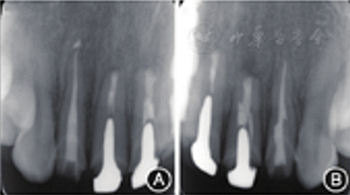

見圖8,圖9,圖10,圖11。分別于術(shù)后3、6個(gè)月時(shí)復(fù)查根尖X線片,8個(gè)月時(shí)復(fù)查錐形束CT并分別進(jìn)行臨床檢查。復(fù)查結(jié)果顯示根尖病變已愈合,根尖無明顯低密度影。臨床檢查叩診正常,無松動(dòng),牙齦位置無明顯變化。

圖8 術(shù)后3個(gè)月復(fù)查患者根尖X線片 A:根尖病變明顯縮??;B:根尖病變明顯縮小